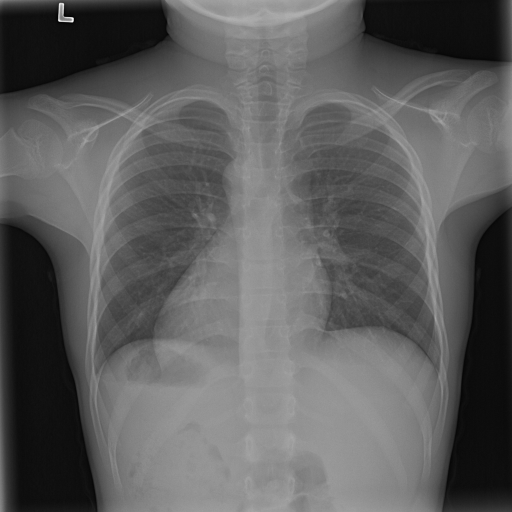

7.1 ϵitalic-ϵ\epsilon-LDP-processed CXR images

(a) Original

case 1

(b) ϵ=103HWitalic-ϵsuperscript103𝐻𝑊\epsilon=10^{3}\cdot H\cdot W

(c) ϵ=102HWitalic-ϵsuperscript102𝐻𝑊\epsilon=10^{2}\cdot H\cdot W

(d) ϵ=101HWitalic-ϵsuperscript101𝐻𝑊\epsilon=10^{1}\cdot H\cdot W

(e) Original

case 2

(f) ϵ=103HWitalic-ϵsuperscript103𝐻𝑊\epsilon=10^{3}\cdot H\cdot W

(g) ϵ=102HWitalic-ϵsuperscript102𝐻𝑊\epsilon=10^{2}\cdot H\cdot W

(h) ϵ=101HWitalic-ϵsuperscript101𝐻𝑊\epsilon=10^{1}\cdot H\cdot W

Figure 1: ϵitalic-ϵ\epsilon-LDP-processed CXR images (we applied the Laplace mechanism in the image domain).

In Fig. 1, we show four ϵitalic-ϵ\epsilon-LDP-processed CXR images of clinical cases obtained with the image domain LDP, which directly imposes the Laplace mechanism on the input image, with different privacy budgets together with the original images. Fig. 2 shows four ϵitalic-ϵ\epsilon-LDP-processed CXR images of clinical cases obtained with DP-GLOW and different privacy budgets together with the original images. In case 1 for DP-GLOW, there is decreased permeability in the bilateral hilar regions. Although this hilar opacity tends to be preserved with a larger privacy budget, the entire image is degraded when the privacy budget becomes 101HWsuperscript101𝐻𝑊10^{1}\cdot H\cdot W. A similar tendency is observed in the images of all the four cases for DP-GLOW; for example, in case 4 with ϵ=101HWitalic-ϵsuperscript101𝐻𝑊\epsilon=10^{1}\cdot H\cdot W, the lung opacity suggesting pneumonia in the right lower lung field is well preserved, while the entire image is degraded.